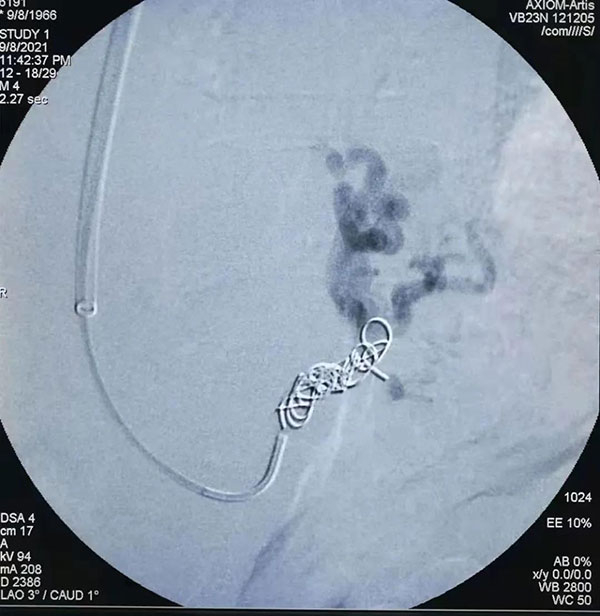

铂金圈栓塞

介入科团队针对患者病情认真讨论后,与家属进行了充分沟通,决定行TIPS手术。手术中找到患者出血的胃底血管用带纤维的铂金圈进行栓塞,栓塞后效果满意,沿导丝引入TIPS覆膜支架系统释放支架,并用球囊反复扩张至凹迹消失,造影确认食道胃底静脉主干栓塞。由导管室护士陪同下安返病房。手术后牛先生生命体征平稳,意识清楚,非常感激在场医生。